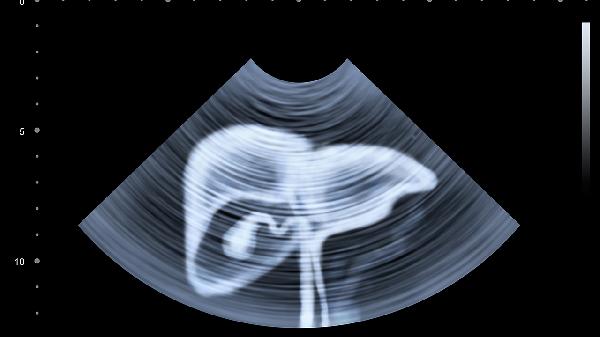

肝癌晚期胆汁穿刺引流有什么用

肝癌晚期胆汁穿刺引流主要用于缓解胆道梗阻引起的黄疸、皮肤瘙痒等症状,改善患者生活质量。胆汁引流的作用主要有减轻胆道压力、改善肝功能、缓解消化吸收障碍、降低感染风险、为后续治疗创造条件。